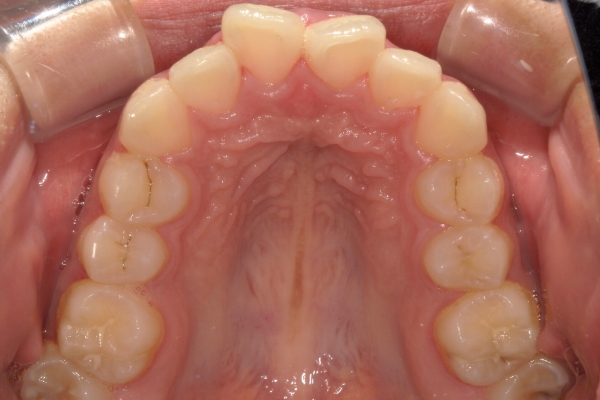

BEFORE

治療前

AFTER

治療後

上顎前歯が1cm近く前方に出ており、叢生を改善しつつ前歯を大きく引っ込めるために上下顎小臼歯の抜歯が必要と診断しました。治療後は、主訴であった前歯の突出と奥歯の噛み合わせのずれが改善され、上下の咬合関係が安定しました。